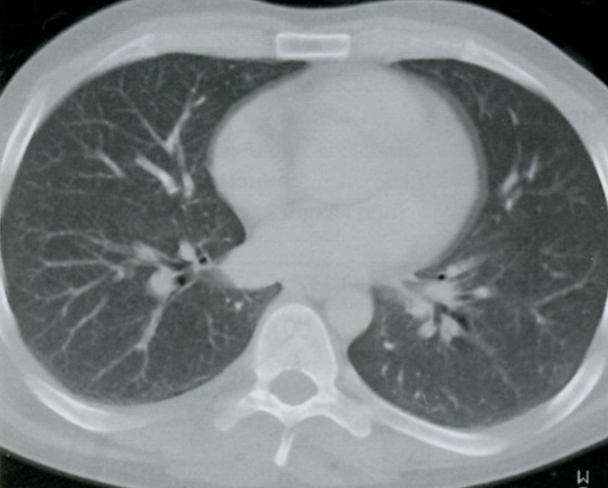

Q

КТ органов грудной клетки высокого разрешения.

Что Вы видите на данном КТ снимке? Постарайтесь вспомнить и назвать все анатомические структуры.

Что отмечено стрелками?

При хронических и прогрессирующих заболеваниях, когда ткань легкого становится более плотной из-за рубцевания и фиброза, податливость и вентиляция легкого уменьшается.

В результате формируется высокое стояние диафрагмы, кистозные изменения в виде “сот” и эмфизема. На ранних стадиях заболевания, когда еще нет признаков поражения на Rx, можно увидеть изменения на спирометрии и КТВР.

A

Стрелками отмечен симптом матового стекла, напоминающий воспалительную экссудацию или неопластическую инфильтрацию.

26 - грудные позвонки

24 - грудина

2 - правое предсердие

7 - восходящая аорта

9 - легочный ствол

3 - левое предсердие

10 - сосуды легких

8 - нисходящая аорта

15 - непарная вена

16 - пищевод